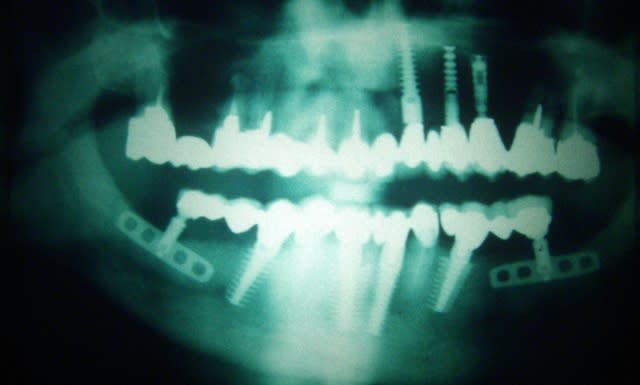

> La démo super bien menée sur un cas bcp plus difficile à gérer

> qu'il y paraissait

> Beaucoup de calme et de sureté et d'humour,dans les moments difficiles et il y

> en a eu, même avec la technique d'expansion condensation les 2 artérioles ont

> essayé de l'embêter, les tables vesti en regard 42 et 32 aussi

> au final 4 implants enfouis et bloqués

> travail très propre et j'ai beaucoup appris

mais je n'aurai du ecouter que mon coeur et en mettre un 5° en 33 ce serait plus joli sur le pano

Le pano pré-op est-il disponible ?

Il y avait des exo ?

C'est quoi le plan de tx pour la prothèse ?

Pourquoi expansion ?

Je crois que la disposition des implants est un peu étrange...